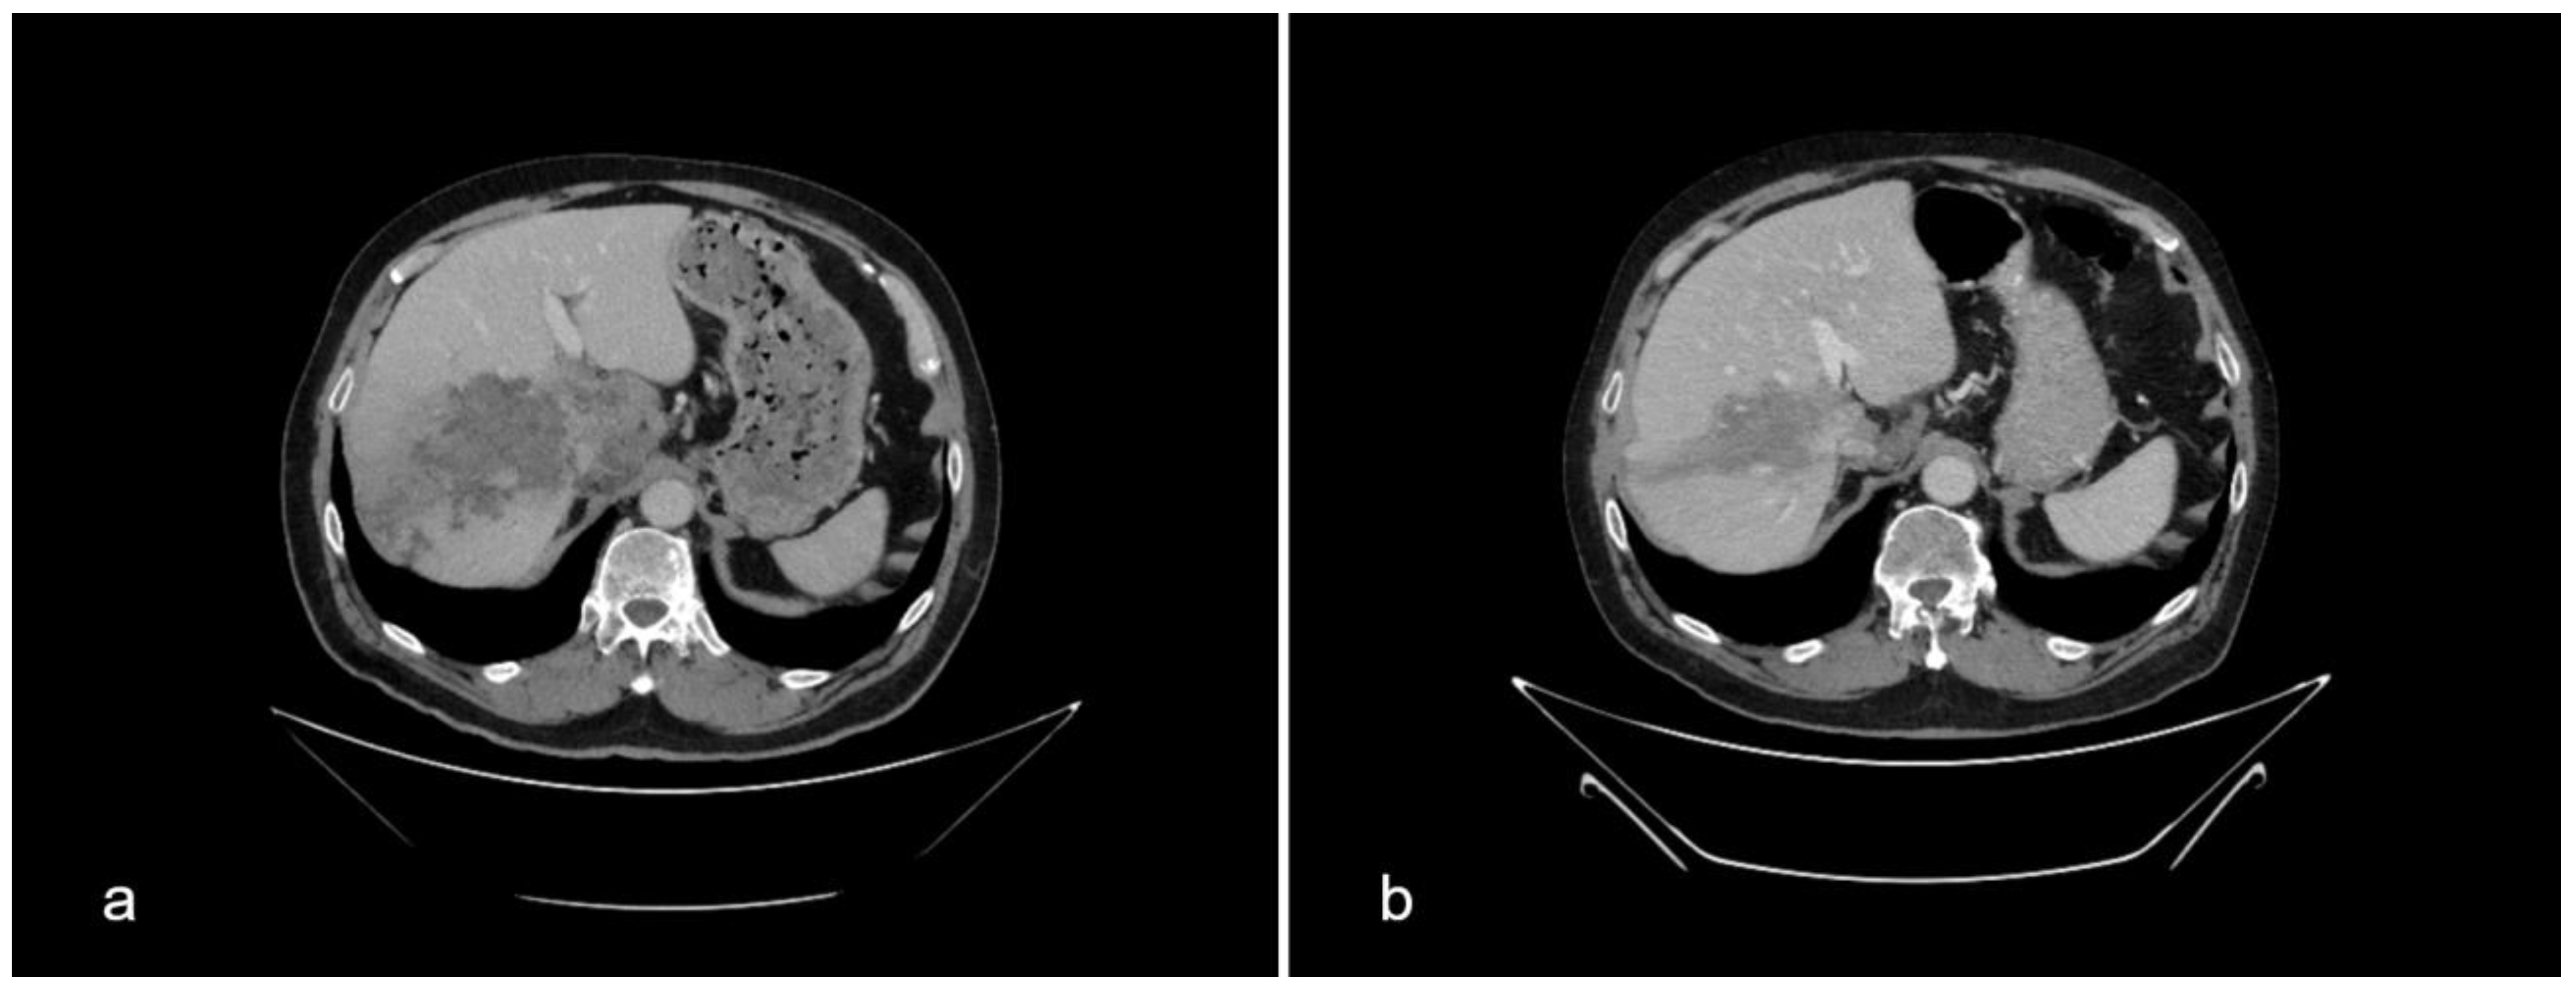

Besides IgAN, the diagnostic evaluation of kidney failure revealed a large infiltrative, poorly delineated, inhomogeneous mass of the right liver lobe (16 × 6.8 × 6.7 cm) and a necrotic nodule measuring 7 × 5 cm next to the celiac trunk (Figure 1a). The described liver lesion was first detected by abdominal ultrasound (US) and then verified by multislice computed tomography (MSCT). The radiographic appearance of the lesion was suspicious of a primary malignant liver tumor. This finding was incidental since our patient had no pain in the right upper abdominal quadrant and he was showing no signs of liver insufficiency, both clinically and according to the laboratory results. Nonetheless, chronic liver disease is often found as an accompanying condition in patients with IgAN.

Figure 1.

Comparison of the liver multislice computed tomography scans at the beginning of albendazole therapy in February 2022 (a) and after 11 months of treatment in January 2023 (b).

The control MSCT in January 2023, following 10 weeks of antibiotic therapy and 11 months of ABZ treatment, showed regression of the lesions. The cystoid lesion of the right liver lobe was now better demarcated than initially and smaller in diameter. The necrotic nodule next to the celiac trunk decreased in size too (Figure 1b).